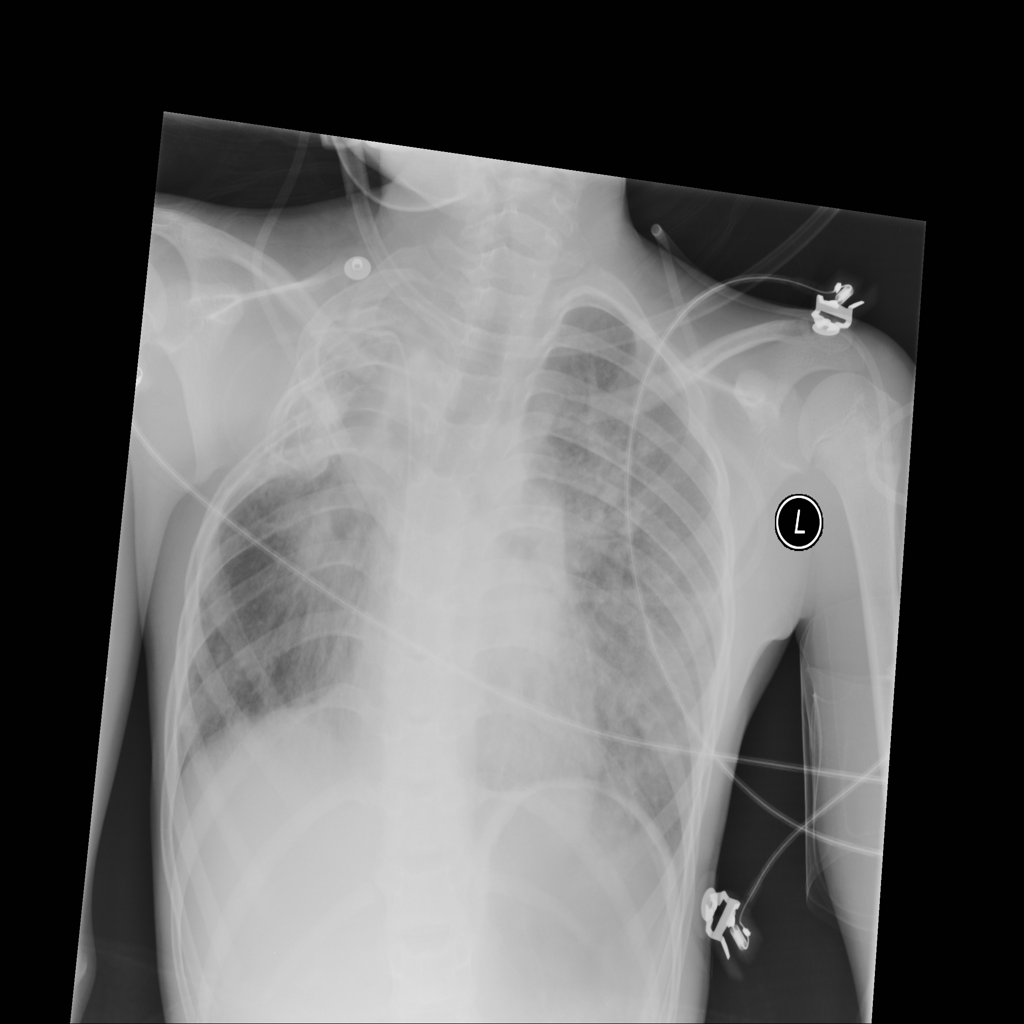

Consolidation

Consolidation refers to air-space filling that makes part of the lung appear denser on imaging.

Showing up to 90 reference images for Consolidation.

PAT-64EB · IMG-015Consolidation

PAT-64EB · IMG-015

AP